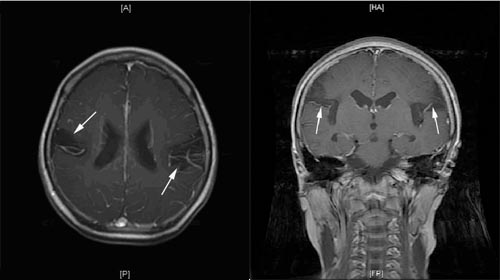

术前双侧颞顶软化灶(↑所示),且该患者24脑电图示异常脑电图全脑弥散分布

行右侧软化灶切除+右侧前颞叶切除+胼胝体切开+皮层软膜下横切术,术后头颅CT表现